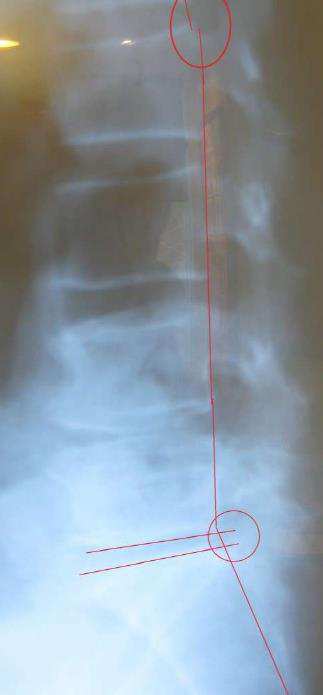

먼저 허리부분의 척추가 일자로 서 버렸고 이는 5번 요추와 천골사이의 디스크로 인한 걸로 보입니다 . 유난히 그 부분의 디스크 간격이 줄어있으며 천추와 요추와의 각이 통증으로 인해 많이 감소된 상태입니다. 또한 흉추부분에서는 후만 현상도 보입니다.